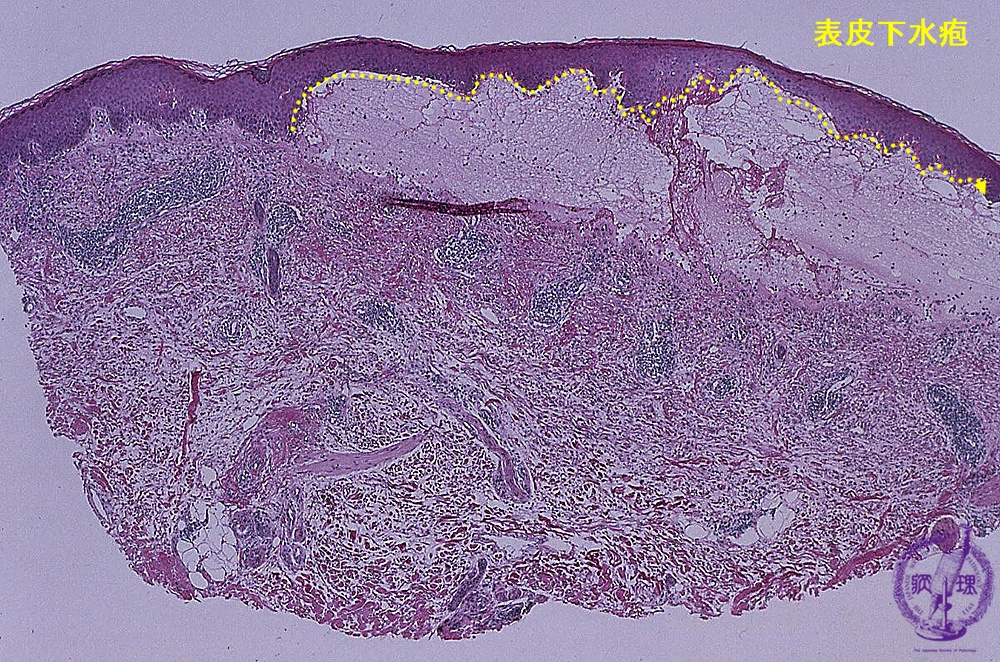

- ★(2)Vesiculobullous disease (Pemphigus vulgaris)

Microscopic image (Bullous pemphigoid): Subepidermal separation corresponds to the bullae. Biopsy taken from the edge of the bullae clearly shows the separation